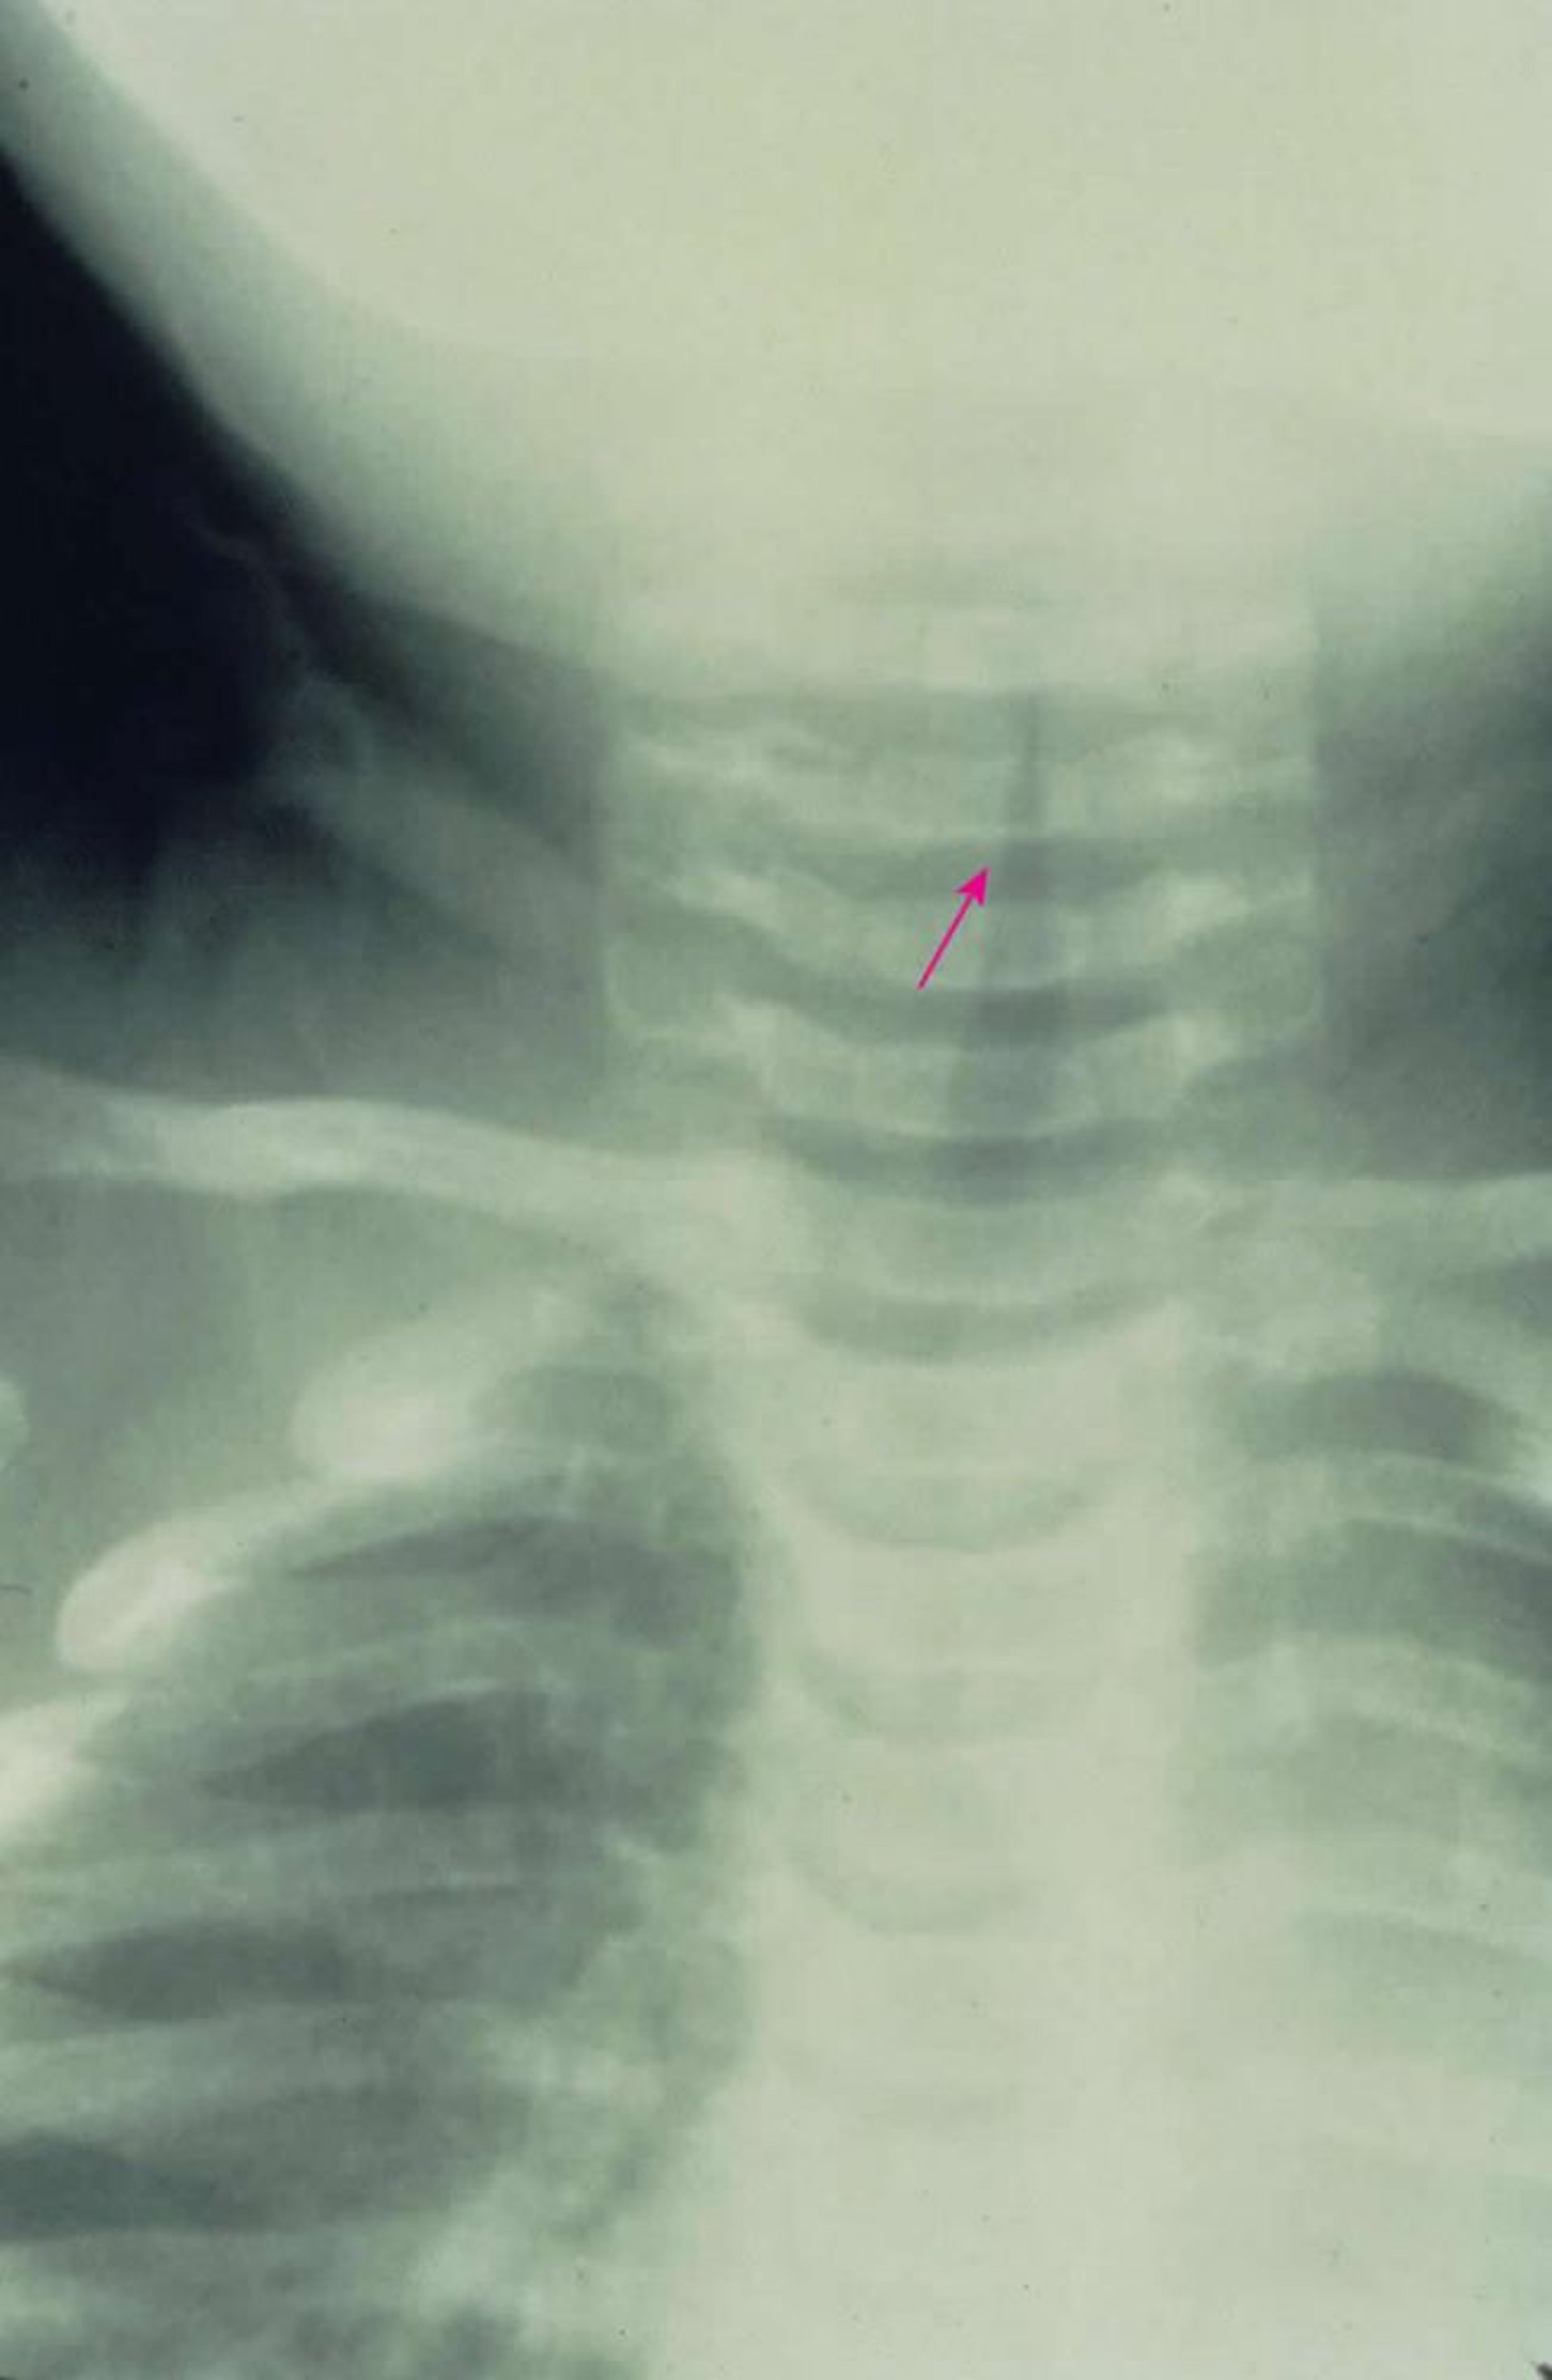

Croup subglótico

Esta radiografía anteroposterior muestra un estrechamiento subglótico característico de la vía aérea (signo del campanario [flecha]) causado por el croup.

Image provided by Clarence T. Sasaki, MD.